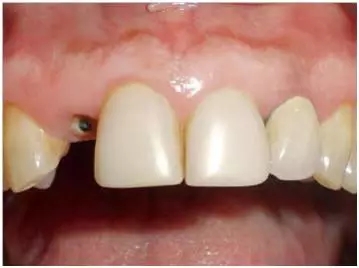

口內(nèi)檢查(圖1至4);

圖1:外傷9天后的臨床檢查:12牙牙冠在釉牙骨質(zhì)界水平處折斷。部分折斷面被牙齦覆蓋,可以看到中央有折斷的金屬根樁(鈦)。11和21牙由復(fù)合樹(shù)脂貼面修復(fù),22牙由金屬烤瓷冠修復(fù)。